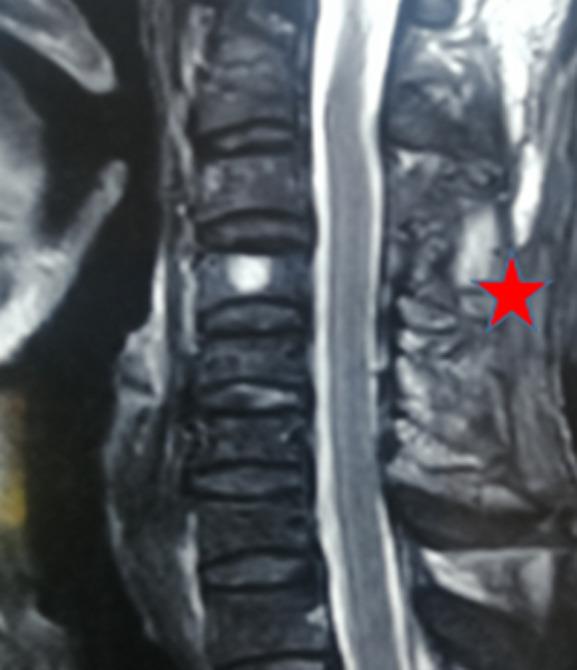

Post-traumatic spinal epidural cervical hematoma is defined as a collection of blood at the level of the epidural space following a trauma. It remains a rare presentation. We report here the case of a cervical epidural hematoma extending from C3 to C5, in a 55-year-old patient victim of a public traffic accident admitted one hour after trauma. Computed Tomography (CT) scan found a compressive epidural hematoma extending C3 to C5; the patient underwent a posterior surgical approach, which allowed to evacuate the hematoma. This rare clinical entity is an emergency diagnosis and management, which needs collaboration between, Intensive Care Unit (ICU) specialists, neurosurgeons, neuroradiologists, and physiotherapists for good outcomes and follow-up.

创伤性颈椎硬膜外血肿是指创伤后硬膜外腔出现血液积聚。它仍然是一种罕见的表现。我们在此报告一例 55 岁患者的病例,该患者在交通事故后 1 小时内入院,颈椎硬膜外血肿从 C3 延伸至 C5。计算机断层扫描(CT)发现 C3 至 C5 有压迫性硬膜外血肿;患者接受了后路手术,血肿得以清除。这种罕见的临床实体是一种紧急诊断和治疗,需要重症监护病房(ICU)专家、神经外科医生、神经放射科医生和物理治疗师的合作,以获得良好的结果和随访。